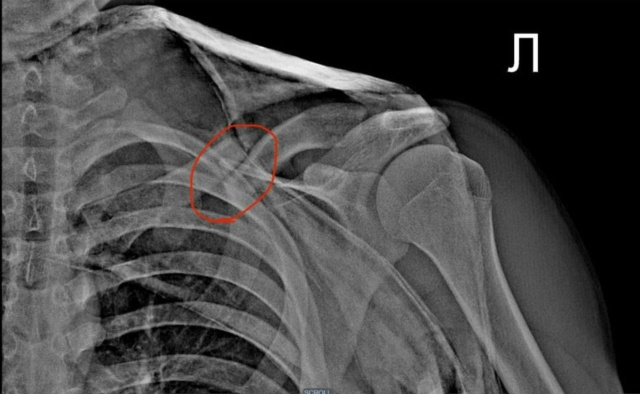

РЕКОМЕНДАЦИИ ТРАВМАТОЛОГА-ОРТОПЕДА: ПЕРЕЛОМ КЛЮЧИЦЫ У ДЕТЕЙ

• выраженное смещение отломков;

• угроза повреждения кожи (когда фрагмент кости «давит» изнутри);

• открытый перелом;

• повреждение сосудов или нервов;

При необходимости оперативного лечения в детской практике часто применяется малоинвазивный остеосинтез — например, фиксация ключицы эластичным стержнем TEN или спицей. После выполнения остеосинтеза мягкие ткани послойно ушиваются, на кожу накладывается атравматический косметический шов, что способствует благоприятному заживлению и формированию аккуратного послеоперационного рубца.